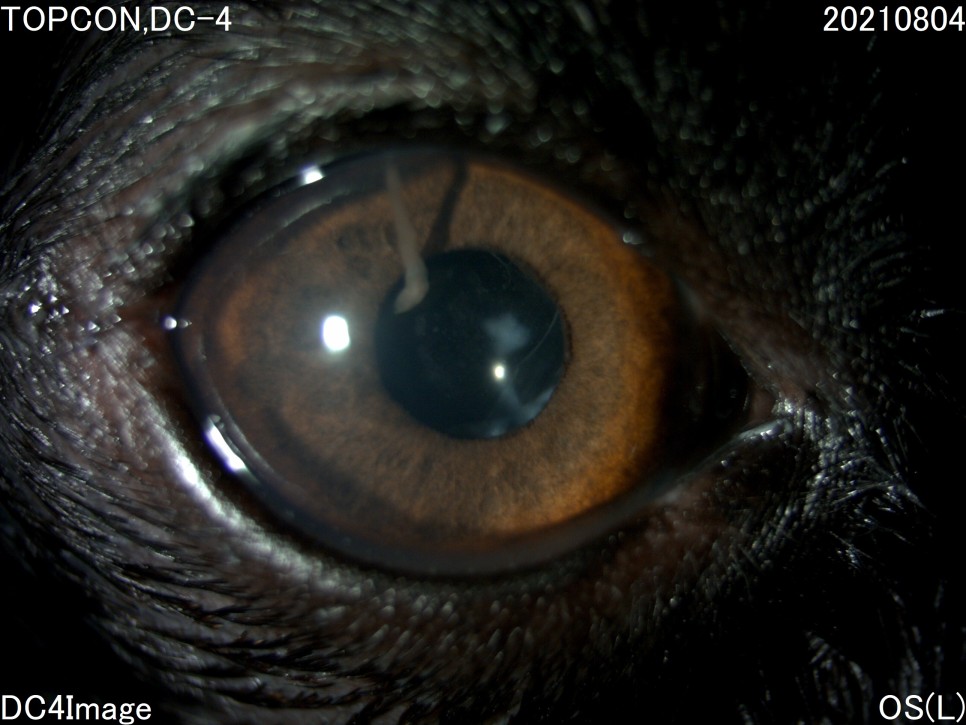

- 세극등 현미경 검사

양안의 백내장이 심하게 진행되고 있었지만 다행히도 당뇨병 관리를 하고 있는 전주 24시 동물병원은 당뇨병 관리 뿐만 아니라 눈 관리도 계속해 주셨기 때문에 내원 당시에는 양안 모두 심한 포도막염은 없었습니다.

그러나 왼쪽 눈은 백내장 단계 중 4기인 과성숙 단계로 진행되었으며, 이전에 앓고 있던 심한 포도막염에 의해 홍채의 일부가 수정체에 유착되어 있는 것이 보였습니다.

백내장이 오래 되거나 염증 반응이 심한 경우는 수정체를 감싸는 낭포 섬유화가 일어나 낭 자체에 백내장 파편이 붙어 있을 수 있는데, 자녀분이 바로 그런 상태였습니다.이런 경우 수술이 어려울 뿐만 아니라 수술 후 합병증의 발생률도 더욱 높아질 수 있습니다.